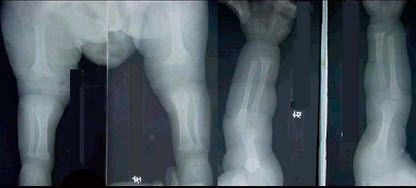

E.胸腔积液

男,15岁,从楼梯上滑倒,足部扭伤,结合图像,最可能的诊断是()

A.腓骨骨折

B.胫腓骨骨折

C.胫骨骨折

D.距骨骨折

E.跟骨骨折